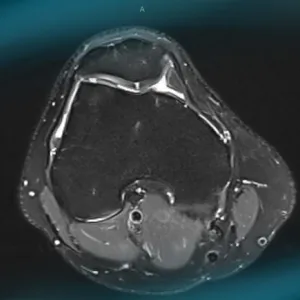

Frane Bukvić presents the case of a 34-year-old orthopaedic surgeon suffering from a symptomatic chondral ‘kissing’ lesion of patella and trochlea... How would manage this condition?